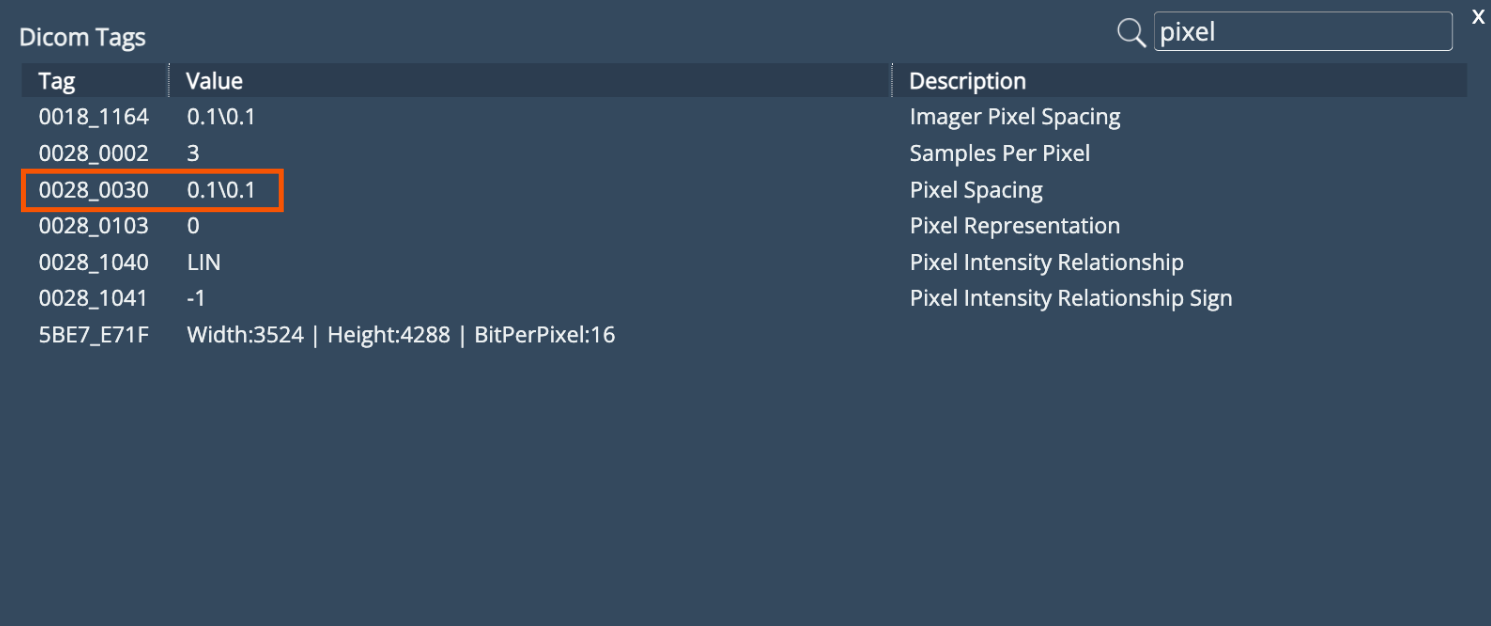

Image Calibration Enhancement

Previously, images uploaded to the platform were not calibrated by default. With this update, the system now extracts the Pixel Spacing value from the DICOM tag to apply a calibration factor, ensuring that images are uploaded with the correct scale.